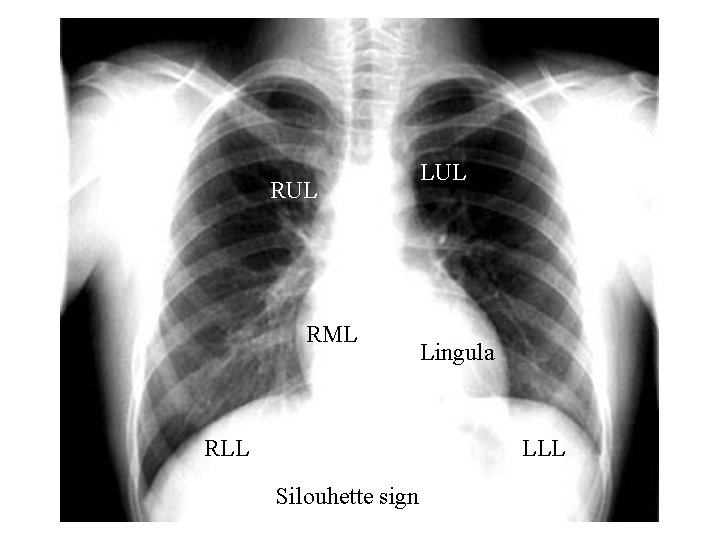

RUL RML RLL LUL Lingula LLL Silouhette sign

Silouhette sign